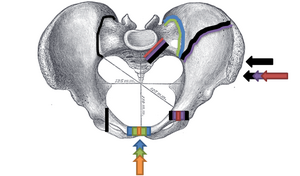

Таз делят на два отдела: верхний, более широкий — большой таз (лат. pelvis major), и нижний, более узкий — малый таз (лат. pelvis minor), разделённые пограничной линией, проходящей через мыс крестца, дугообразные линии подвздошных костей, гребни лобковых костей и верхний край лобкового симфиза.

- Conjugata anatomica или diameter recta (анатомическая конъюгата/прямой диаметр верхней апертуры) — между мысом крестца и верхним краем лобкового симфиза — 11,5 (10,8) см

- Diameter transversa (поперечный диаметр верхней апертуры) — наиболее отдалённое между пограничными линиями — 13,5 (12,8) см

- Diameter obliqua (косой диаметр) — между расположенными с противоположных сторон крестцово-подвздошным суставом и подвздошно-лобковым возвышением — 12,0-12,6 (12,0-12,2) см

- Прямой размер таза — между стыком II и III крестцовых позвонков и задней частью середины лобкового симфиза — 12,2 (10,8) см

- Поперечный размер таза — между центрами вертлюжных впадин — 11,5 (10,8)

- Прямой диаметр нижней апертуры — между вершиной копчика и нижним краем лобкового симфиза — 9,5 (7,5)

- Поперечный диаметр нижней апертуры — между седалищными буграми — 10,8 (8,1) см